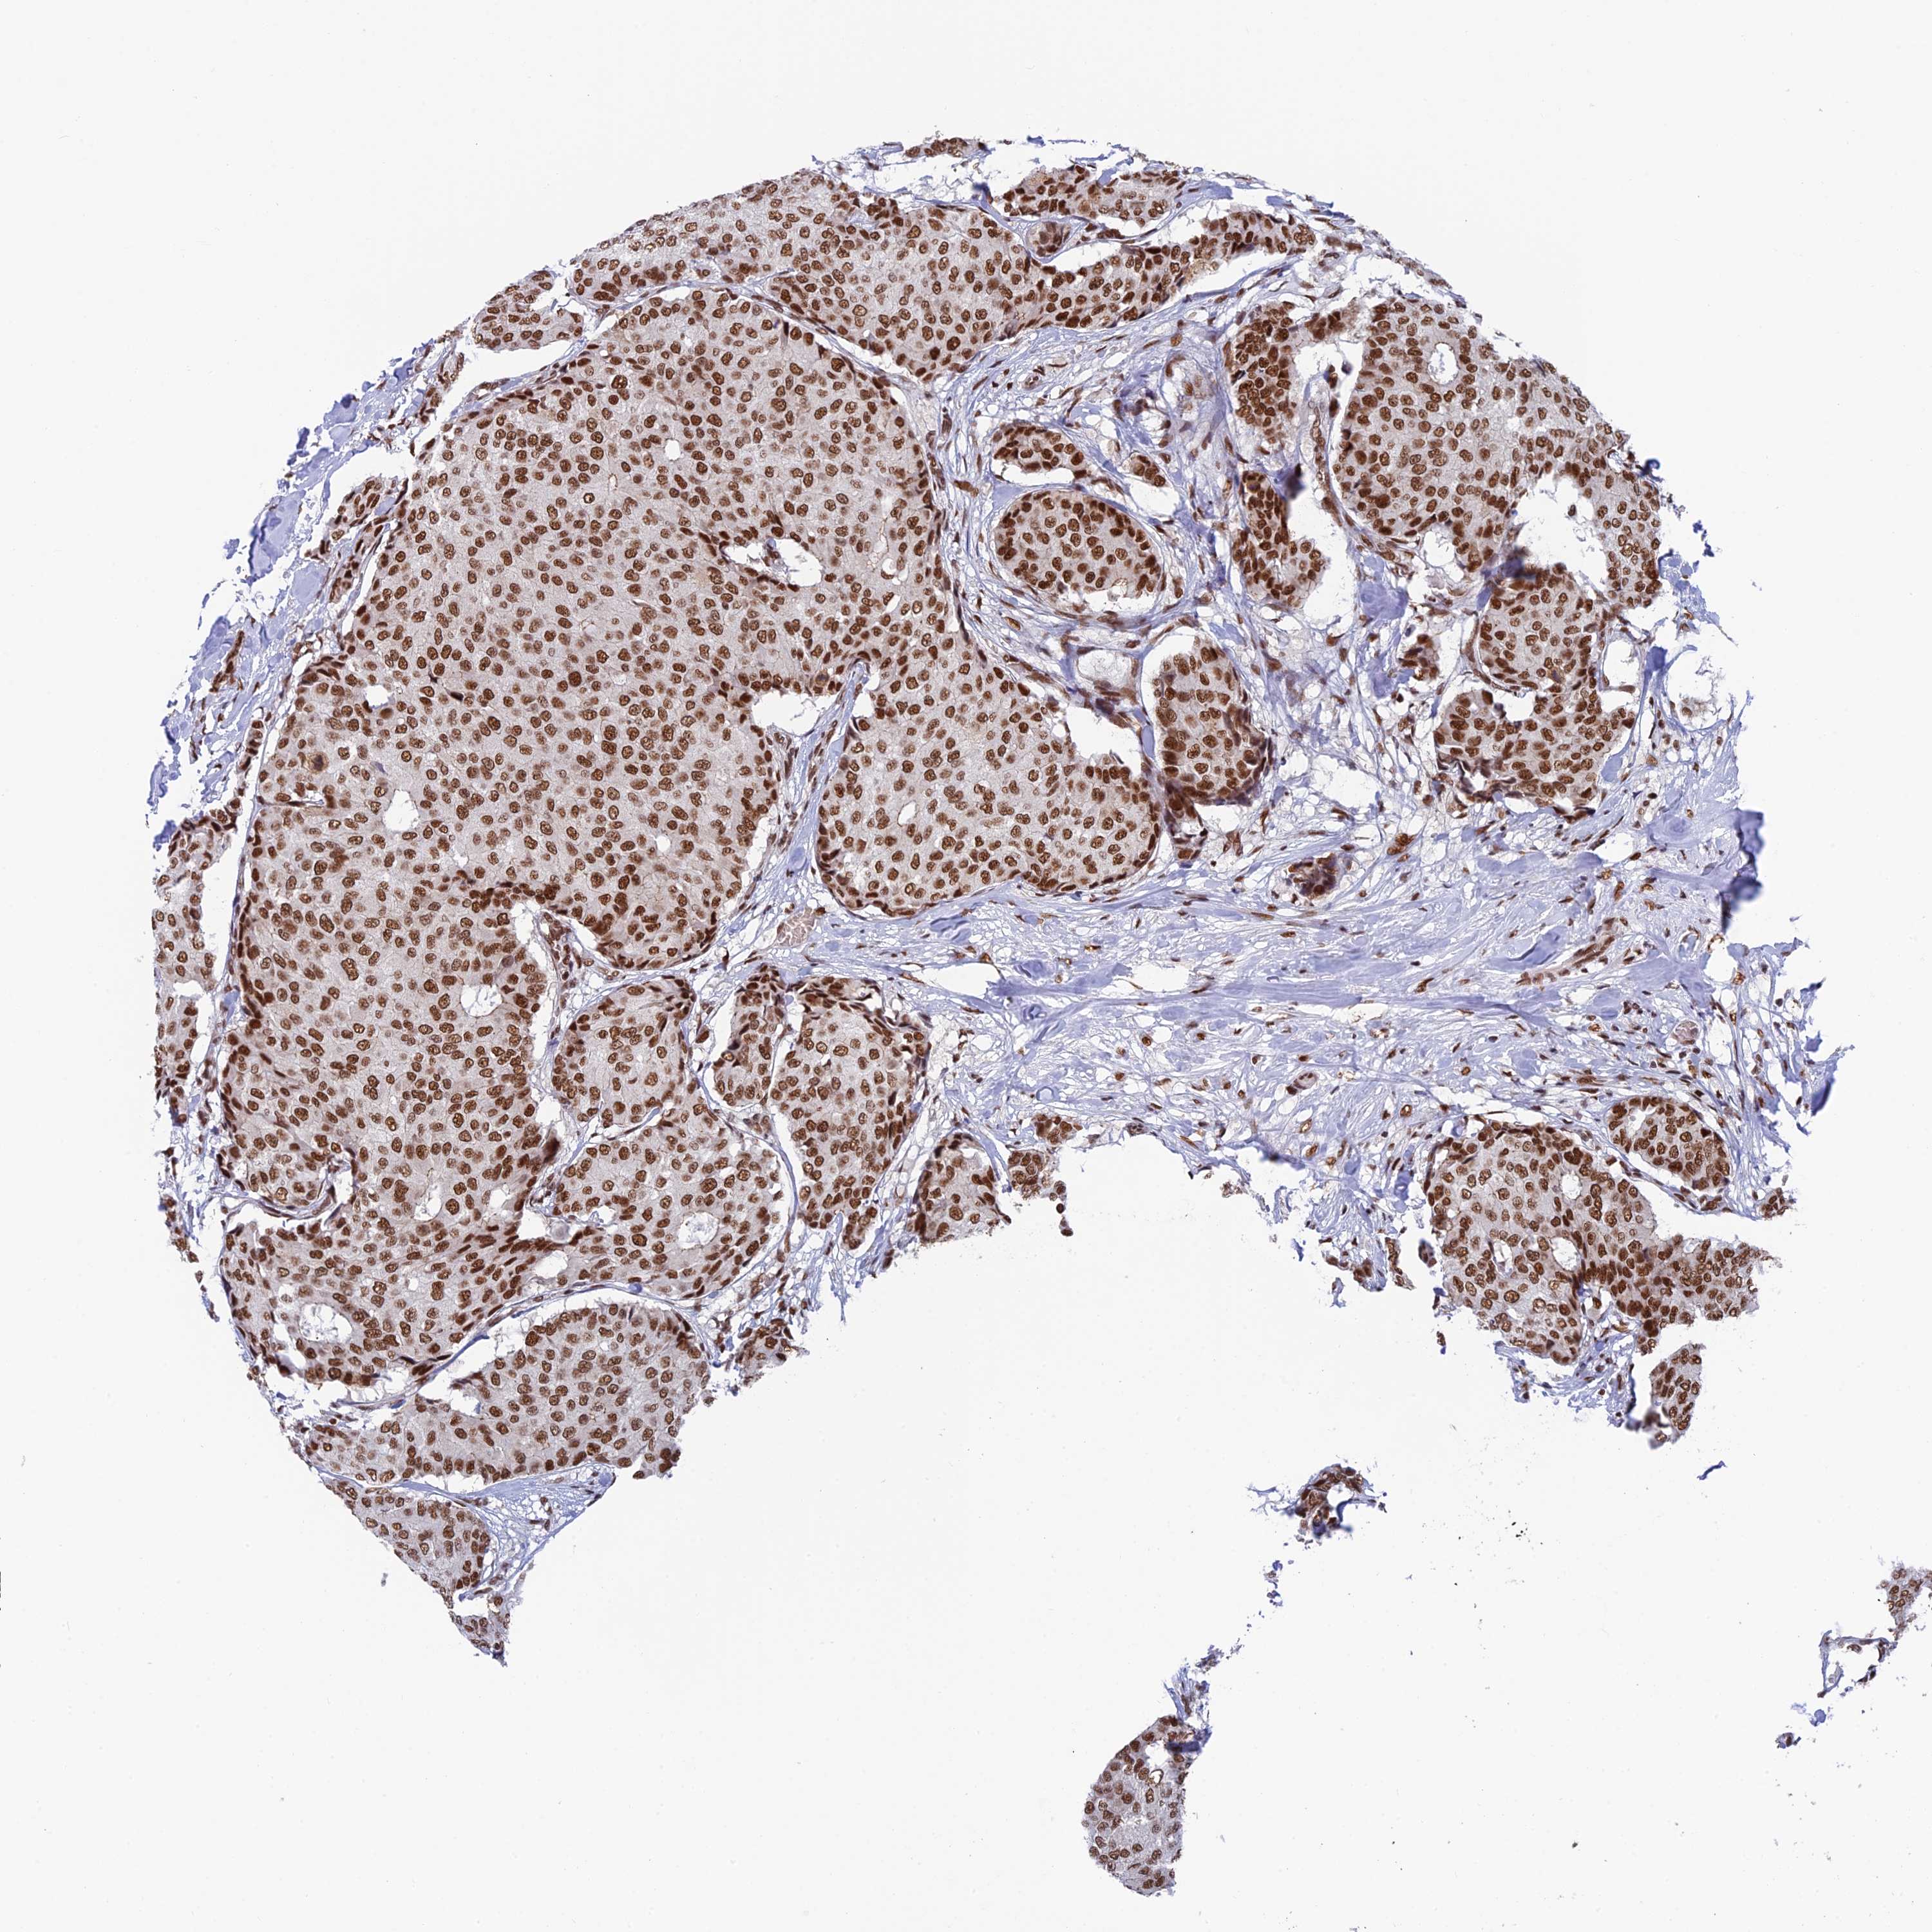

BRCA TCGA BRCA VALIDATION PROTEIN EXPRESSION

ANTIBODIES

AND

VALIDATION